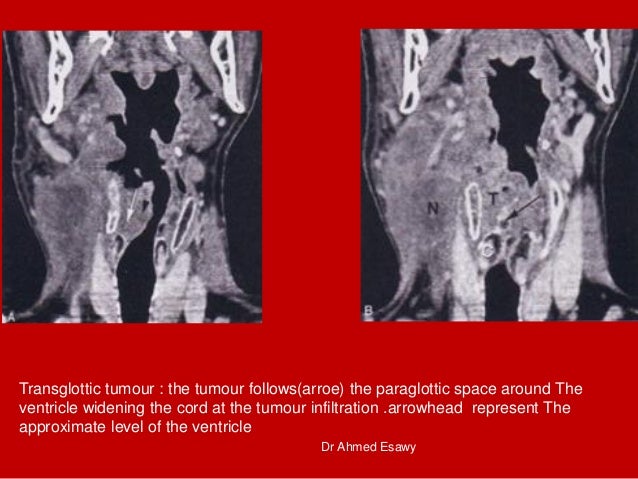

44. 44. Transglottic tumour : the tumour follows(arroe) the paraglottic space around The ventricle widening the cord at the tumour infiltration .arrowhead represent The approximate level of the ventricle Dr Ahmed Esawy